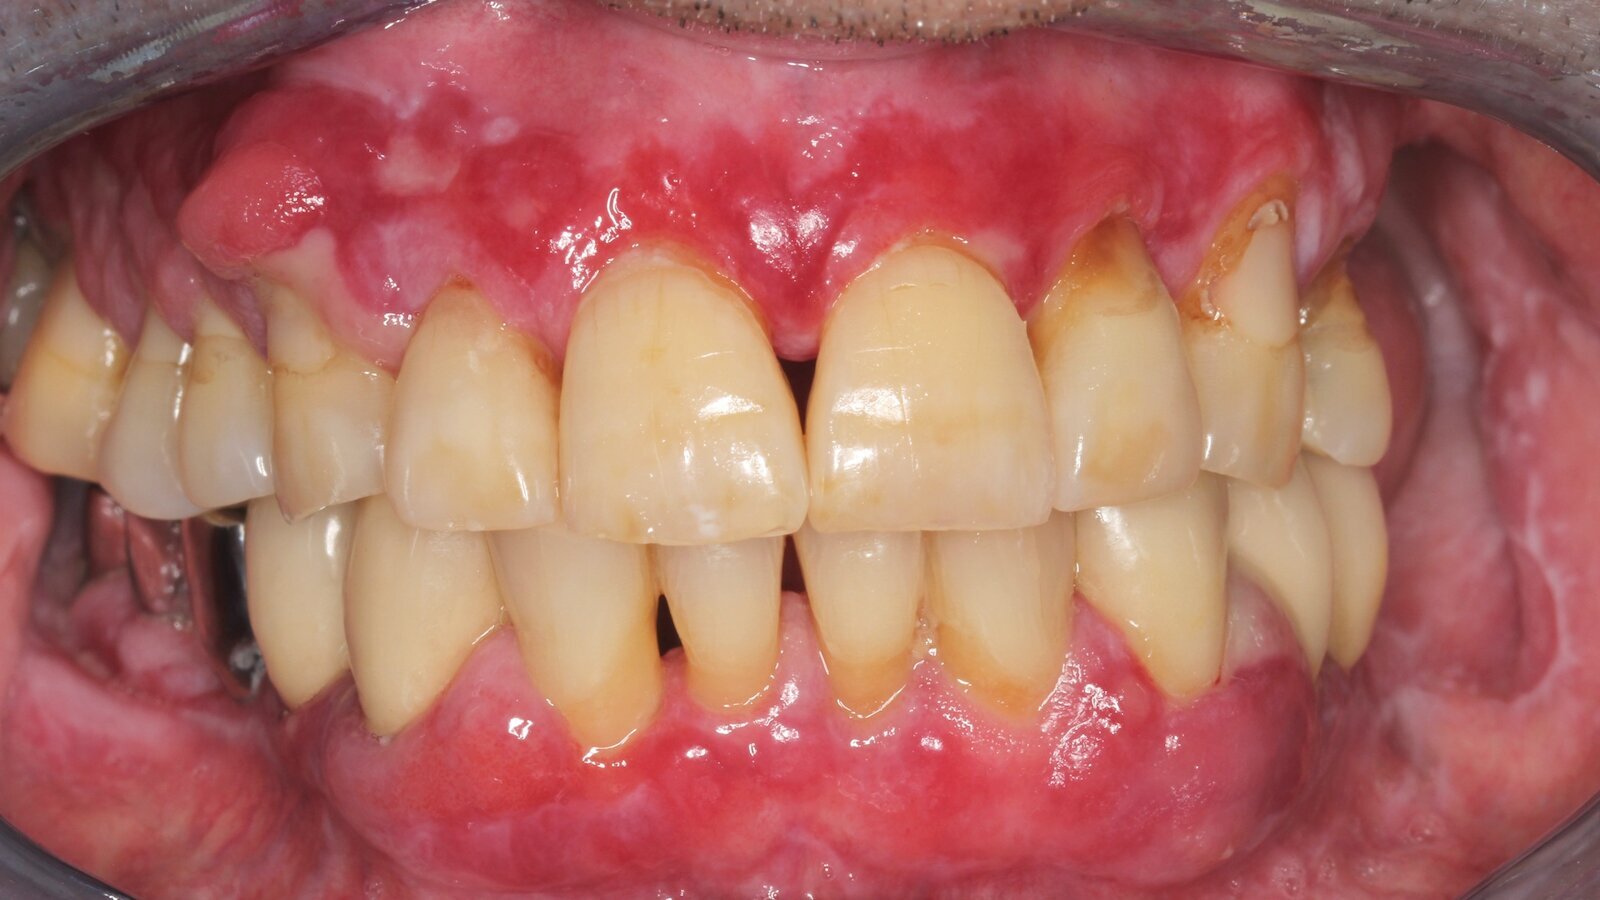

Se presenta en la consulta un paciente de 71 años con trasplante de riñón e hipertensión. Debido a su historia médica, necesita tratamiento continuo con ciclosporina para suprimir el sistema inmunitario y amlopidina para bajar la presión arterial. Además, el paciente relata encías sensibles y sangrantes. Desde el punto de vista de la salud oral, hay dientes restaurados con ocho piezas faltantes, hiperplasia gingival pronunciada, periodontitis en fase II de grado B con bolsas activas y una caries inicial en la pieza 22. En la evaluación del riesgo de caries se establece un riesgo medio (API 60). Para la sesión de profilaxis se hacen las siguientes recomendaciones.

• Con base en la historia médica, se identifica un riesgo de complicaciones importante. Debido al trasplante de riñón, el paciente está inmunodeprimido (toma ciclosporina), tiene el sistema inmunitario debilitado y necesita profilaxis para infecciones (recomendación: 2g de amoxicilina como antibiótico 1h antes de la sesión). Al mismo tiempo, el tratamiento médico a largo plazo hace que el paciente tenga un mayor riesgo de enfermedad, dado que la hiperplasia gingival detectada está asociada con la medicación que toma.

• Se debe abordar la situación del paciente, especialmente en lo que se refiere a educación y motivación. La hiperplasia gingival dificulta su higiene oral en casa. La mayor susceptibilidad a infecciones y el avance y nueva formación de hiperplasias debe explicársele de forma sencilla. Al mismo tiempo, deben explicarse las técnicas de higiene adecuadas para sus necesidades individuales.

• Se recomienda un intervalo de control posterior más corto, de tres a cuatro meses. Esto se debe principalmente a la hiperplasia gingival asociada con la medicación, la situación asociada de cuidado difícil y el alto riesgo de progresión de la periodontitis.